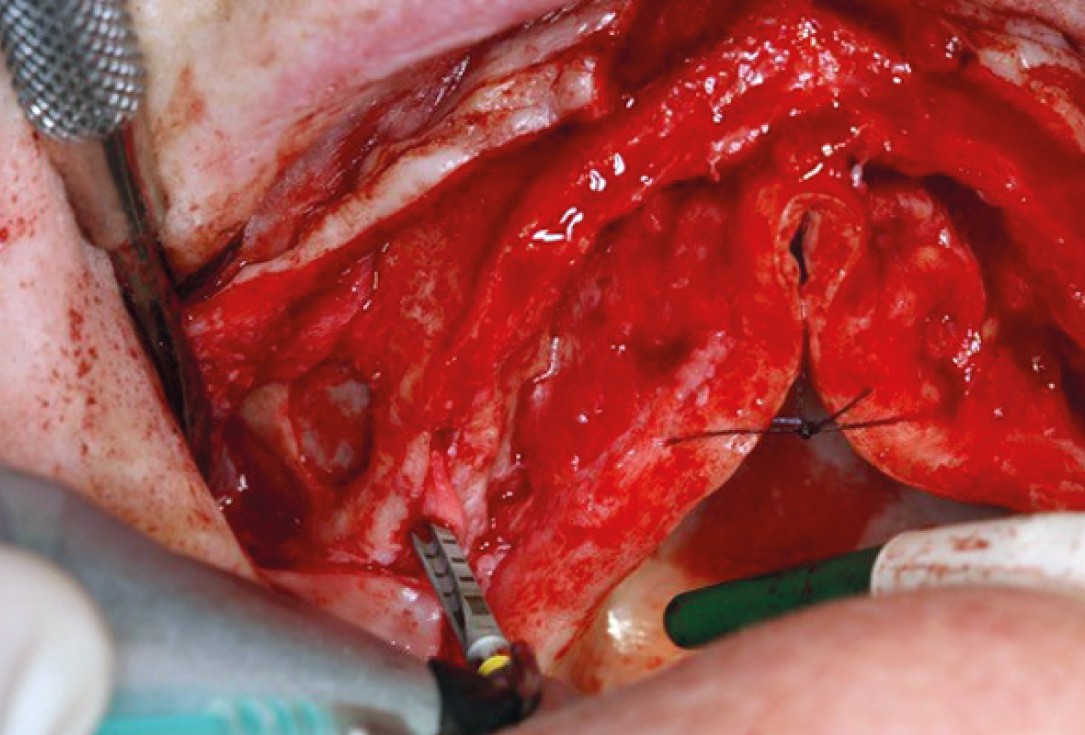

08/11 - Flap preparation in the mandible

Sinus lift with maxresorb® inject - Dr. E. Valdimarsson